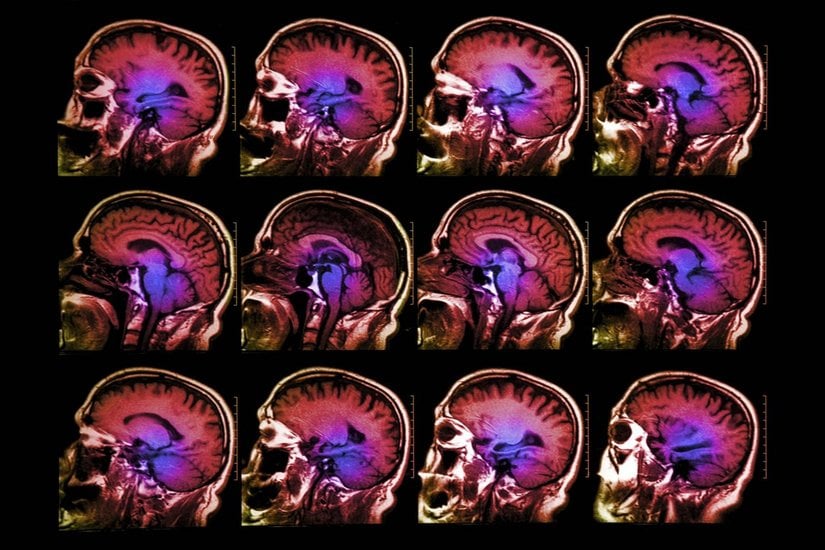

Nörobilim alanı yakın tarihimizde geliştirilen fMRI sayesinde hareketlendi. İnsanlar fMRI makinesinin içine uzandıkları zaman, bilim insanları kişinin gerçek zamanlı beyin aktivitelerini görebiliyor. Bu, beynimizin gri maddesi üzerindeki sırları açığa çıkaracağını vaat eden bir beyin okuma türüdür.

Önceki çalışmalarda tespit edilemeyen şey, kişinin aslında ne hissediyor olduğuydu. Carnegie Mellon Üniversitesi’nden açıklanan bir yeni araştırma ise, duyguların aslında sinirsel aktiviteye bağlı olduğunu haritalandırdı. Bu bunu yaparken de fMRI makinası kullanıldı.

CMU’nun Dietrich Beşeri ve Sosyal Bilimler Kolejinden araştırmacılar, deneyde kullandıkları aktörlere öfke, tiksinti, kıskançlık, şehvet, gurur, üzenti, utanç gibi kelimeleri gösterildi. Bundan sonra, aktörlere gördükleri kelimelerdeki duygusal hale gelmeleri istendi ve beyinleri fMRI tarafından görüntülendi ve bilgisayar tarafından sonuçlar çıkarıldı.

Bu taramaya göre, bilgisayar, duyguları anımsatacak seri fotoğraflarını gören aktörlerin duygularını düzgünce tahmin edebildi. Her duygunun özel bir sinirsel imzası bulunmaktadır. Bilgisayarın öğrendiği beyin aktivitesinin desenleri bu bireylerle sınır değil. Aktörlerin beyinlerinin taramasına göre, bilgisayar model teste daha önce hiç girmemiş olan yeni aktörlerin duygularını aydınlattı.

Yeni araştırma duyguların objektif bir şekilde ölçülmesine bir temel oluşturuyor. “Beyinde aktif olan farklı desenlerin pozitif ve negatif duygular olmak üzere ayrıldığını fark ettik.” diyor Kassam. Beynin duygusal yapıtaşları modeli oluşturarak, araştırmacılar duygusal rahatsızlıklardaki düşüncenin farkının ne olduğuna dair bir bakış açısı kazanabildi.